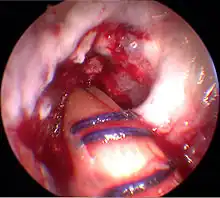

Arthroscopie

L'opération proprement dite commence par l'introduction de l'arthroscope dans le genou du patient. Ceci permet de confirmer définitivement le diagnostic de rupture de LC. Les autres blessures, en particulier celles des ménisques, peuvent être soignées avant la reconstruction du LC.

Prélèvement du transplant

Le premier temps de l'opération est le prélèvement du transplant. Une incision d'environ 4 cm dans la peau sur la partie interne de la tête du tibia, au-dessus de la «patte d'oie» permet le prélèvement successif sur les tendons semi-tendineux et gracile. Les prélèvement sont faits sur les deux tendons avec un « couteau à tendon », et ont une longueur d'environ 28 cm. Ils sont pré-tendus avec un dispositif spécial, et cousus ensemble en un cordon multiple, par exemple quadruple. La longueur du transplant est alors de 7 cm, avec un diamètre d'environ 7 mm. Le transplant est alors cousu au moyen d'un fil spécial dans les deux trous internes d'un disque ovale à quatre trous (endobouton). Ce fil spécial n'est pas résorbable.

Élimination des restes de ligament croisé et percement des canaux osseux

Les restes du LCA rompu sont éliminés sous arthroscopie. Pour cela, on utilise un outil motorisé de découpe et d'aspiration. À l'aide d'un appareil à positionner, la position pour le percement d'un canal à travers la tête du tibia est déterminée, et le trou est fait. La même procédure est appliquée au percement à travers le fémur. Ce canal se rétrécit vers le haut et a une longueur d'environ 35 mm. La partie plus large de ce canal est destinée à recueillir le transplant, la partie étroite à faire passer l'accrochage du transplant.

Enfilage du transplant

Le transplant est inséré au moyen de deux fils de traction du bas vers le haut dans les trous percés. Au moyen d'une vis creuse, le transplant est fixé au fémur. L'extrémité sortant du canal du tibia est pré-tendue et fixée par coincement avec une vis d'interférence (vis delta). Puis les orifices opératoires sont recousus, en laissant un drain aspiratif. La durée de l'opération est environ de 45 à 90 min.